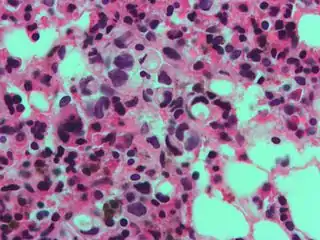

Signet ring cell, as seen in a case of colon adenocarcinoma with mucinous features, showing a tumor cell with a vacuole of mucin. H&E stain.

The name of the cell comes from its appearance; signet ring cells resemble signet rings. They contain a large amount of mucin, which pushes the nucleus to the cell periphery. The pool of mucin in a signet ring cell mimics the appearance of a finger hole and the nucleus mimics the appearance of the face of the ring in profile.